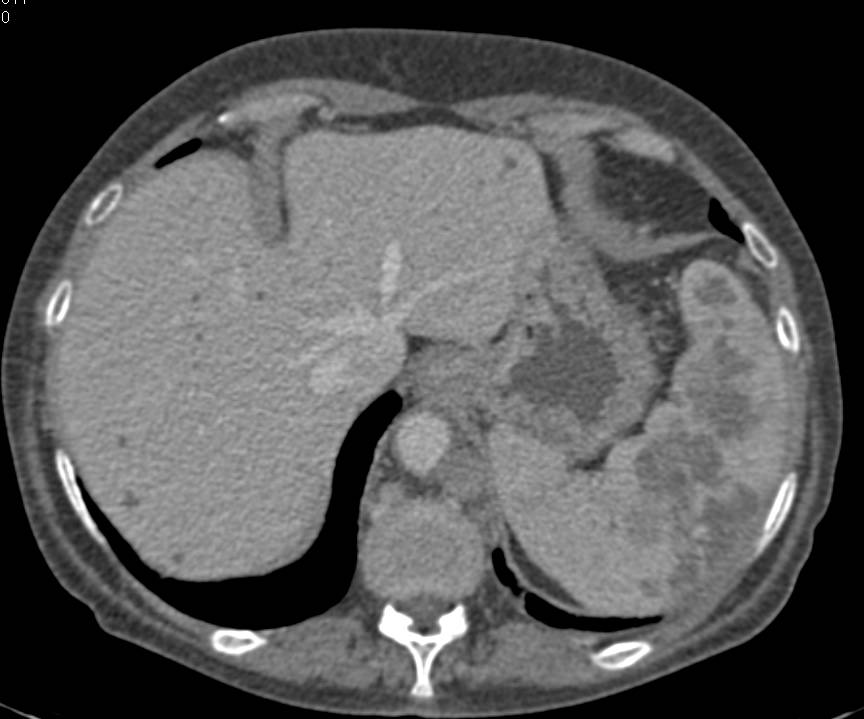

Unusual Case of Pancreatic Adenocarcinoma with Splenic Metastases and Cystic Adenopathy